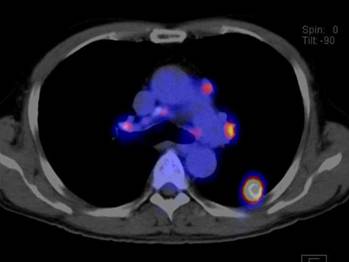

大腸がんの患者さんの実際の写真を示します。図1のPET画像では、腫瘍の活動性がよくわかります。図2のCT画像では、腫瘍の形がわかりますが、これだけでは診断は難しい像です。図3のPET-CT画像では、腫瘍の形と活動性が両方ともわかり、自信を持って大腸がんと診断できます。

肺がんの患者さんの実際の写真を示します。図4、図5のPET-CT画像で、肺がんが小さいリンパ節に転移している様子が明瞭に示され、治療方針を立てるのに役立ちます。

![]() |

| 図 4 PET - CT 画像 | 図 5 PET - CT 画像 |